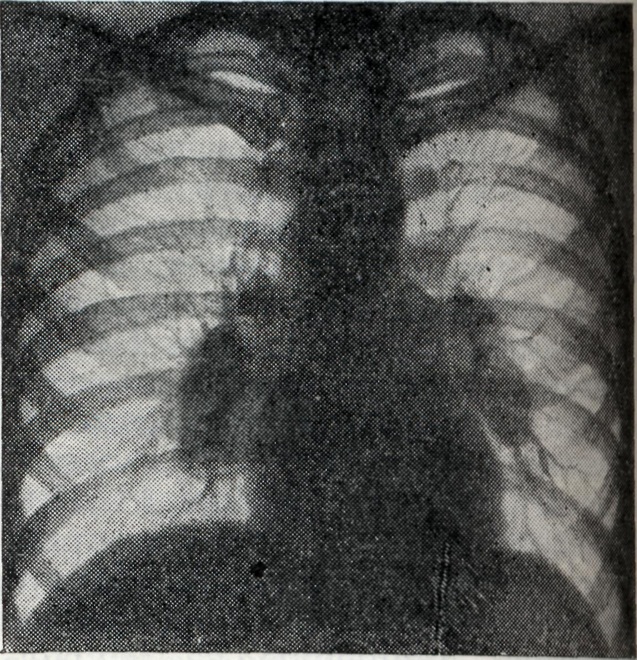

Бронхагенное рассеивание казеозного материала ведёт к развитию тяжёлых бронхопневмоний (лобулярио-казеозных). Осложнения. Течение Б. нередко осложняется плевритом (железисто-плевральный синдром); характерны междолевые экссудативные плевриты (чаще при первичном туберкулёзе). При большом увеличении группы лимф, узлов может возникнуть ателектаз сегмента или доли лёгкого. Длительное существование ателектазов может привести к фибротизации спавшегося участка с образованием бронхоэктазов. Диагноз ставится на основании комплексного клинико-рентгенологического обследования, анамнеза (контакта с туберкулёзным больным), характера туберкулёзной интоксикации. Подтверждением туберкулёзной этиологии процесса в висцеральных грудных лимф, узлах является туберкулиновая проба (см. Туберкулинокагностика). При туберкулёзном Б. чаще встречается резко положительная туберкулиновая проба. При туберкулёзном Б. с тяжёлым осложнённым течением туберкулиновые пробы могут быть слабоположительными (состояние анергии). Выявлению клинически не диагностируемых и осложнённых форм Б. способствует также бронхоскопия (см.), при к-рой нередко обнаруживаются инфильтративные изменения стенки бронха и свищи соответственно расположению патологически изменённого лимф. узла. Основной метод диагностики Б. — рентгенологический. Рентгенодиагностика имеет целью установить наличие увеличенных или уплотнённых висцеральных грудных лимф, узлов. При этом руководствуются принципом целенаправленного рентгенологического исследования области средостения путем применения различных способов послойной рентгенографии (томография лучами повышенной жесткости с продольным, поперечным и косым направлением размазывания теней, с выделением толстых слоев — зонография). Послойная рентгенография должна быть многопроекционной (см. Полипозиционное исследование). Особенно ценнов диагностике поражений труднодоступных для выявления групп лимф. узлов (бифуркационных, левых трахео-бронхиальных, парааортальных, артериального протока, бронхо-пульмональных) использование не только прямых и боковых, но и косых проекций с поворотом грудной клетки на 45° в правом и левом лопаточном положении. На послойных рентгенограммах выявляются сочетанные поражения бронхов и лимф, узлов, а в отдельных случаях — лимфо-бронхиальные свищи и компрессионные стенозы. При опухолевидной форме Б. перифокальные явления в прилегающей лёгочной ткани обычно отсутствуют. Тень корня увеличена, менее структурна, отдельные сосудистые стволы корня плохо различимы (рис. 1). Проекции бронхов менее отчётливы, тень корня почти сливается с тенью средостения. Наружная волнообразная или бугристая граница деформированного корня проецируется в виде отчётливой, хотя и не всегда резкой линии, что зависит от отсутствия или наличия воспалительных изменений в капсуле лимф, узлов. При одностороннем опухолевидном Б. изменения корня противоположного лёгкого менее выражены (рис. 2), на стороне поражения лёгочный рисунок несколько усилен, прилежащие листки междолевой плевры уплотнены (рис. 3). При вовлечении в процесс медиастинальной плевры бугристые наружные контуры корня или средостения могут исчезать. Тень средостения расширена, имеет гладкие контуры.